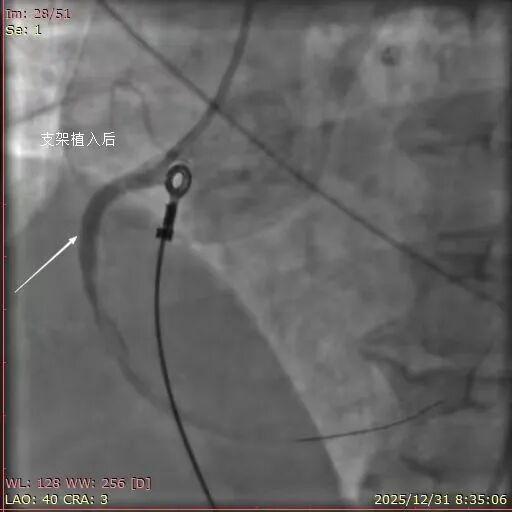

2025年12月31日,7点30分患者王某,女,57岁,突发胸痛10小时就诊于平度市第三人民医院胸痛中心,值班医生迅速为患者完善床旁心电图检查,检查结果提示“急性下壁心肌梗死”。与患者家属进行了充分沟通,并建议行急诊冠脉介入治疗。患者家属在了解情况后,毫不犹豫地同意并签字。随后,患者被送入导管室。术中造影结果显示:右冠状动脉近段99%狭窄,可见血栓影,TIMI血流2级。

与患者家属沟通并获得同意后,医护人员迅速为患者介入诊疗,成功在右冠近段置入4.0×23mm支架一枚。